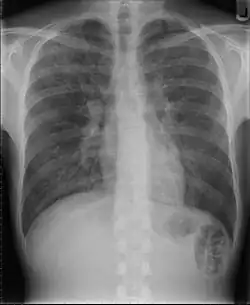

Beim Verdacht auf eine Pneumonie werden in der Regel zwei Röntgenbilder der Lunge angefertigt. Im Röntgenbild stellen sich schlecht belüftete Areale hell dar. Diese können z. B. auf eine Lungenentzündung hindeuten. Diese Veränderung (Infiltrat) entsteht durch die Einwanderung von Leukozyten (Infiltration) und die entzündlich bedingte Schwellung. Sind die luftleitenden Teile der Lunge und die Lungenbläschen nicht betroffen – wie bei einer interstitiellen Pneumonie (Entzündung des Bindegewebes zwischen den Lungenbläschen) –, stellen sie sich im Röntgenbild dar (positives Bronchopneumogramm). Sind hingegen die Lungenbläschen in dem entzündeten Bereich nicht mehr zu sehen, deutet dies darauf hin, dass sich dort Flüssigkeit befindet und die Entzündung in den Lungenbläschen stattfindet wie z. B. bei einer Lobärpneumonie.